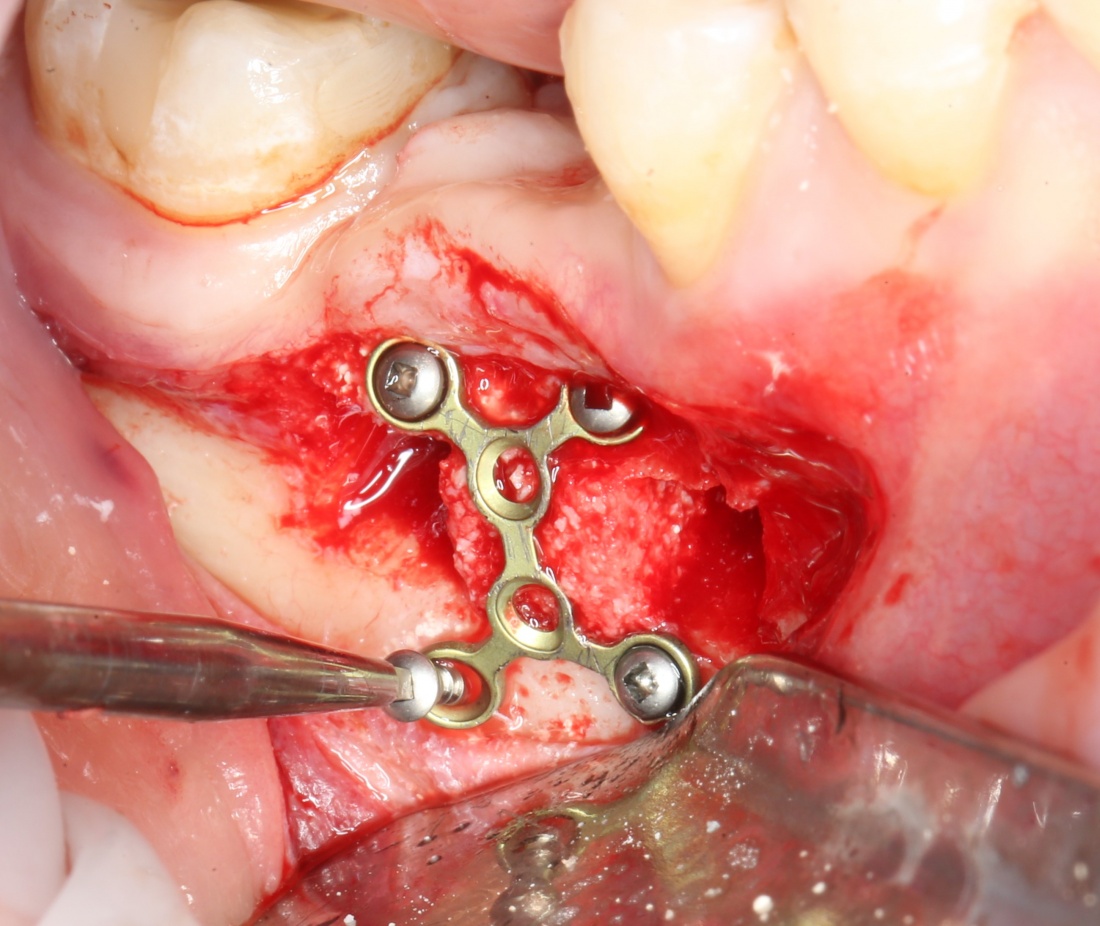

Подготовка костного ложа и фиксация аутотрансплантата

Возвращаемся к основной операционной области. Еще раз посмотрим на альвеолярный гребень, поофигеваем от его ширины и моих грандиозных планов:

На этом месте мне следует дать некоторые пояснения.

Если ты читал мои предыдущие публикации, посвященные остеопластике, то наверняка знаешь, что костное ложе перед фиксацией графта (любого графта) требует некоторой подготовки. В основном она заключается в полном или частичном удалении кортикального слоя и, применительно к АТККФ — адаптации не только блока под ложе, но и ложа под пересаживаемый костный блок. Подробности здесь>>

Ежу понятно, что к необходимости этих манипуляций мы пришли не сразу. А тогда был 2013 год… и у меня были мысли, что подготовка костного ложа нужна не всегда и не всем. Здесь я понадеялся на размер костного дефекта и большую площадь контакта между костным аутотрансплантатом и принимающим ложем. Конечно, сейчас я сделал бы немного по-другому.

Я зафиксировал костный блок практически без адаптации на несколько винтов. Обрати внимание, что винты находятся в зоне, где не планируется установка имплантатов. Фиксация должна быть надежной, поскольку мне еще предстояла подготовка лунок для имплантатов. Трех винтов для этого вполне достаточно.

Дальнейшая адаптация костного блока свелась к сглаживанию острых краев. После чего я приступил к подготовке лунок и установке имплантатов.

Установка имплантатов.

Напомню, что для этой работы я выбрал субкрестальные имплантаты Ankylos C/X. Они прекрасно сочетаются с любым методом остеопластики.

Я не планирую установку супраструктур или коронок, поэтому на уровень первичной стабильности можно положить болт. Даже наоборот — чем меньше крутящий момент при установке, тем лучше. Для имплантатов Ankylos и подобных им, это особенно важно. В общем, момент силы при установке — не более 10-15 Нсм.

Ремарка: имплантаты с предустановленными имплантодержателями хороши тем, что с ними легко контролировать позиционирование имплантатов. В случае с Ankylos С/Х - еще и крутящий момент. Имплантодержатель должен отсоединяться от имплантата с легким щелчком. Если его клинит, и тебе приходится прикладывать для этого усилия, то ты, однозначно, превысил момент силы во время установки имплантата. Следовательно, жди проблем.

Глянем на то, что получилось:

Осталось адаптировать костный блок (убрать острые края), проверить его фиксацию и, при необходимости, добавить винты. Десятисекундное дело.